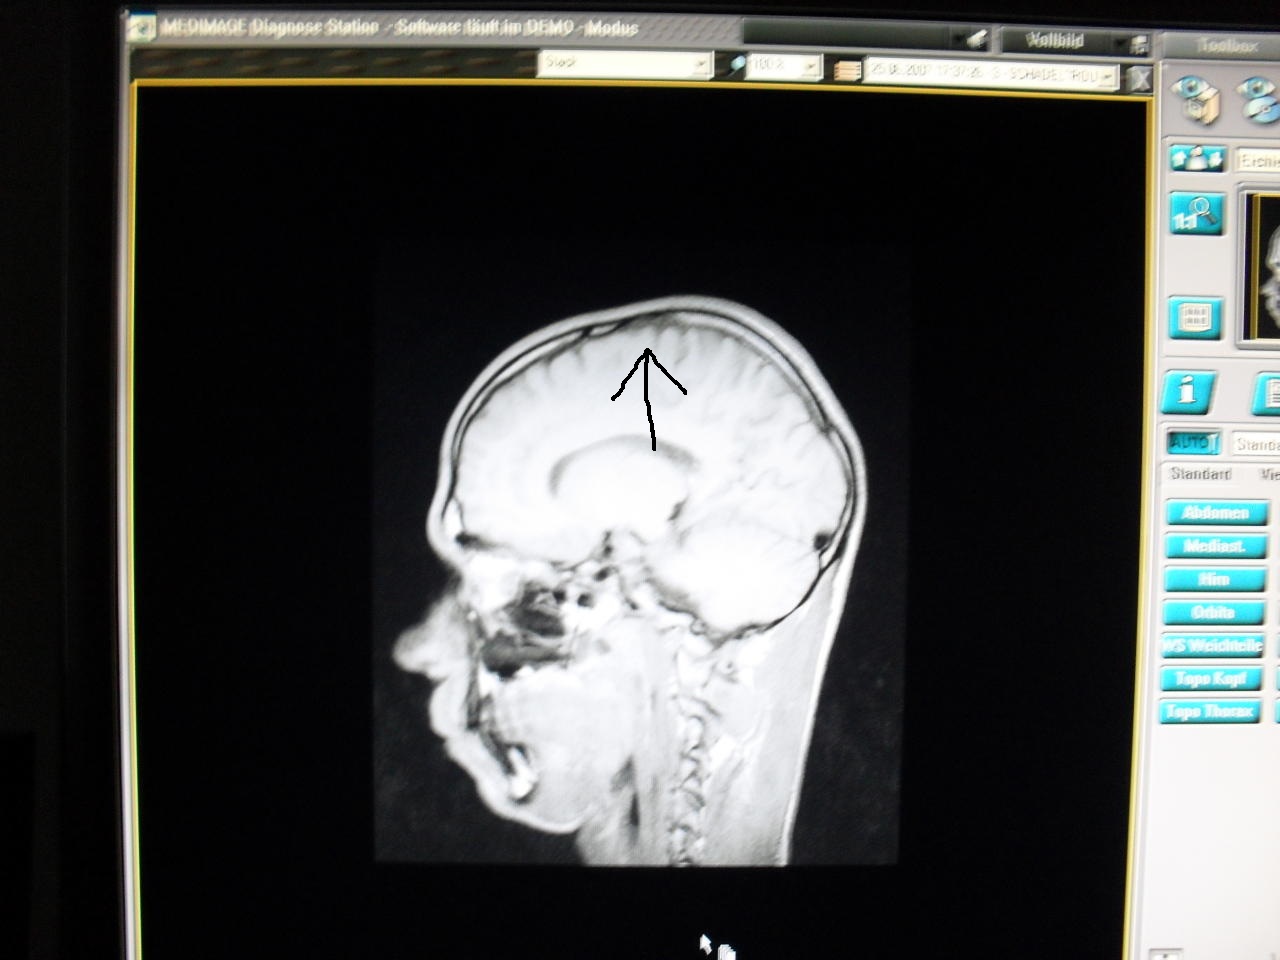

Jedenfalls bin ich mit meinen Nerven am Ende...und will euch mal paar Bilder von meinen MRT zeigen,weil ich der Meinung bin,das es dort diverse Auffälligkeiten nach meinen Standpunkt aus gibt!

Vorn weg möchte ich noch sagen,das ich denke...,das ich unter einen Kindlichen SHT leide,und meine Weichteile angegriffen sein müssen...."dura Mater"....äussere harte Hirnhaut....muss einen weg bekommen haben.

Hier die Bilder...